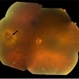

- Optic nerve head granuloma of sarcoidosis with severe infiltration and exudation in the left eye of the same patient #2.